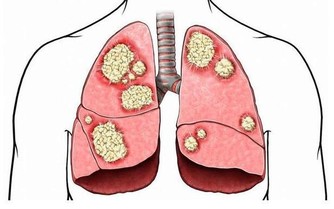

腎臟是人體最重要的代謝器官之一,如果腎臟出現了問題,那麼我們體內的毒素就無法正常代謝,

從而破壞我們機體內環境的穩定,引發很多健康問題。

保護好我們的腎臟,對於我們的健康來說是至關重要的。